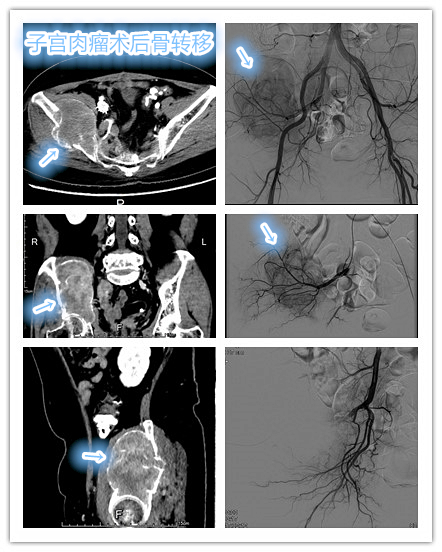

前期先行局部区域动脉化疗栓塞治疗,局部动脉化疗栓塞杀灭、控制肿瘤,同时肿瘤血供短时间内明显减少,为后续局部消融穿刺减低穿刺出血风险及提高消融效率。

骨转移瘤局部动脉化疗栓塞